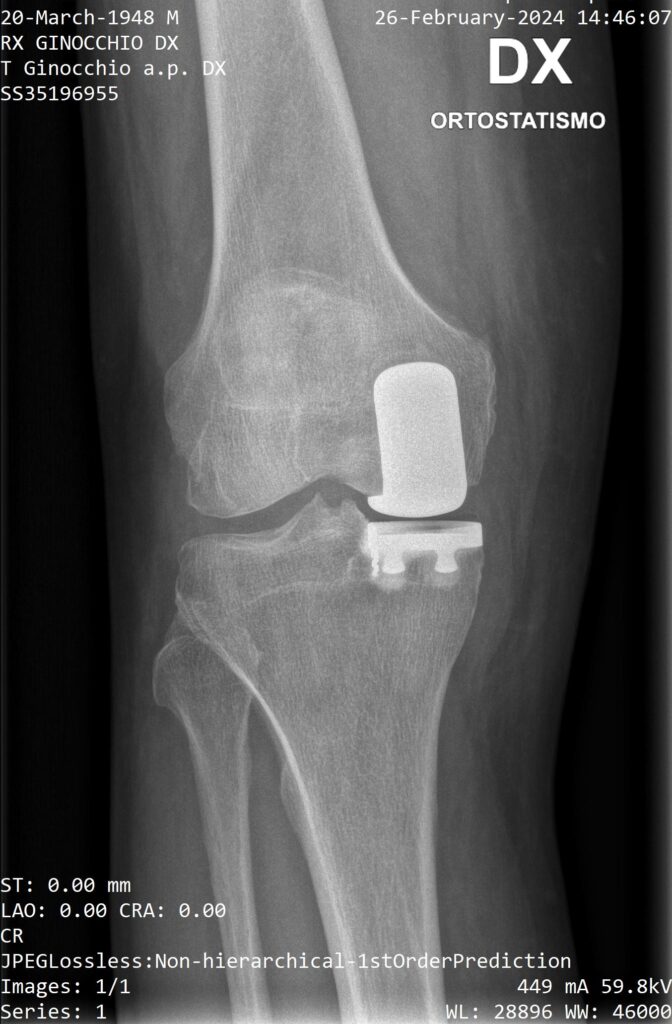

Rx preoperatoria

Rx postoperatoria

Protesi monocompartimentale

In casi selezionati può essere utile l’impianto di una protesi monocompartimentale, considerata la vera protesi di ginocchio mininvasiva. Prevede infatti la sostituzione del solo compartimento danneggiato con componenti protesiche di superficie che rivestono il condilo femorale e l’emipiatto tibiale (mediale o laterale).

Questo tipo di protesi è indicata nell’osteonecrosi del condilo femorale o dell’emipiatto tibiale e nell’artrosi monocompartimentale (che interessa solo una parte del ginocchio, quella mediale o quella laterale).

L’intervento prevede un’incisione di circa 7-8 cm; il decorso postoperatorio è meno impegnativo rispetto a un’artroprotesi totale e il recupero riabilitativo più veloce.